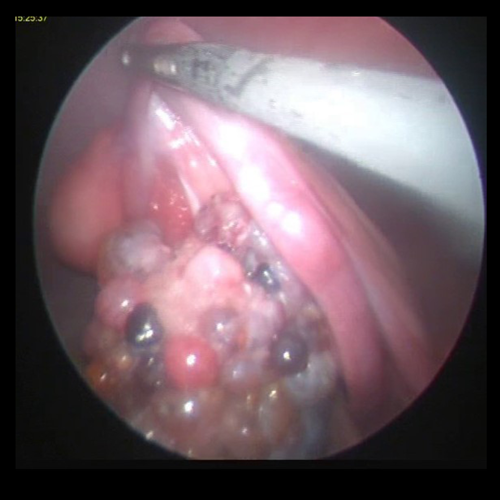

- Practical hands-on experience of laparoscopic surgeries including neutering, gastropexy, liver biopsy, bile aspirate, abdominal exploration and gastrointestinal biopsies

Laparoscopy can be used in veterinary clinics to perform neutering, prophylactic gastropexy, abdominal organ biopsies and much more. Laparoscopy has proven benefits compared to conventional open surgery including: smaller surgical wounds, decreased pain, faster recovery to normal activities and improved outcomes.